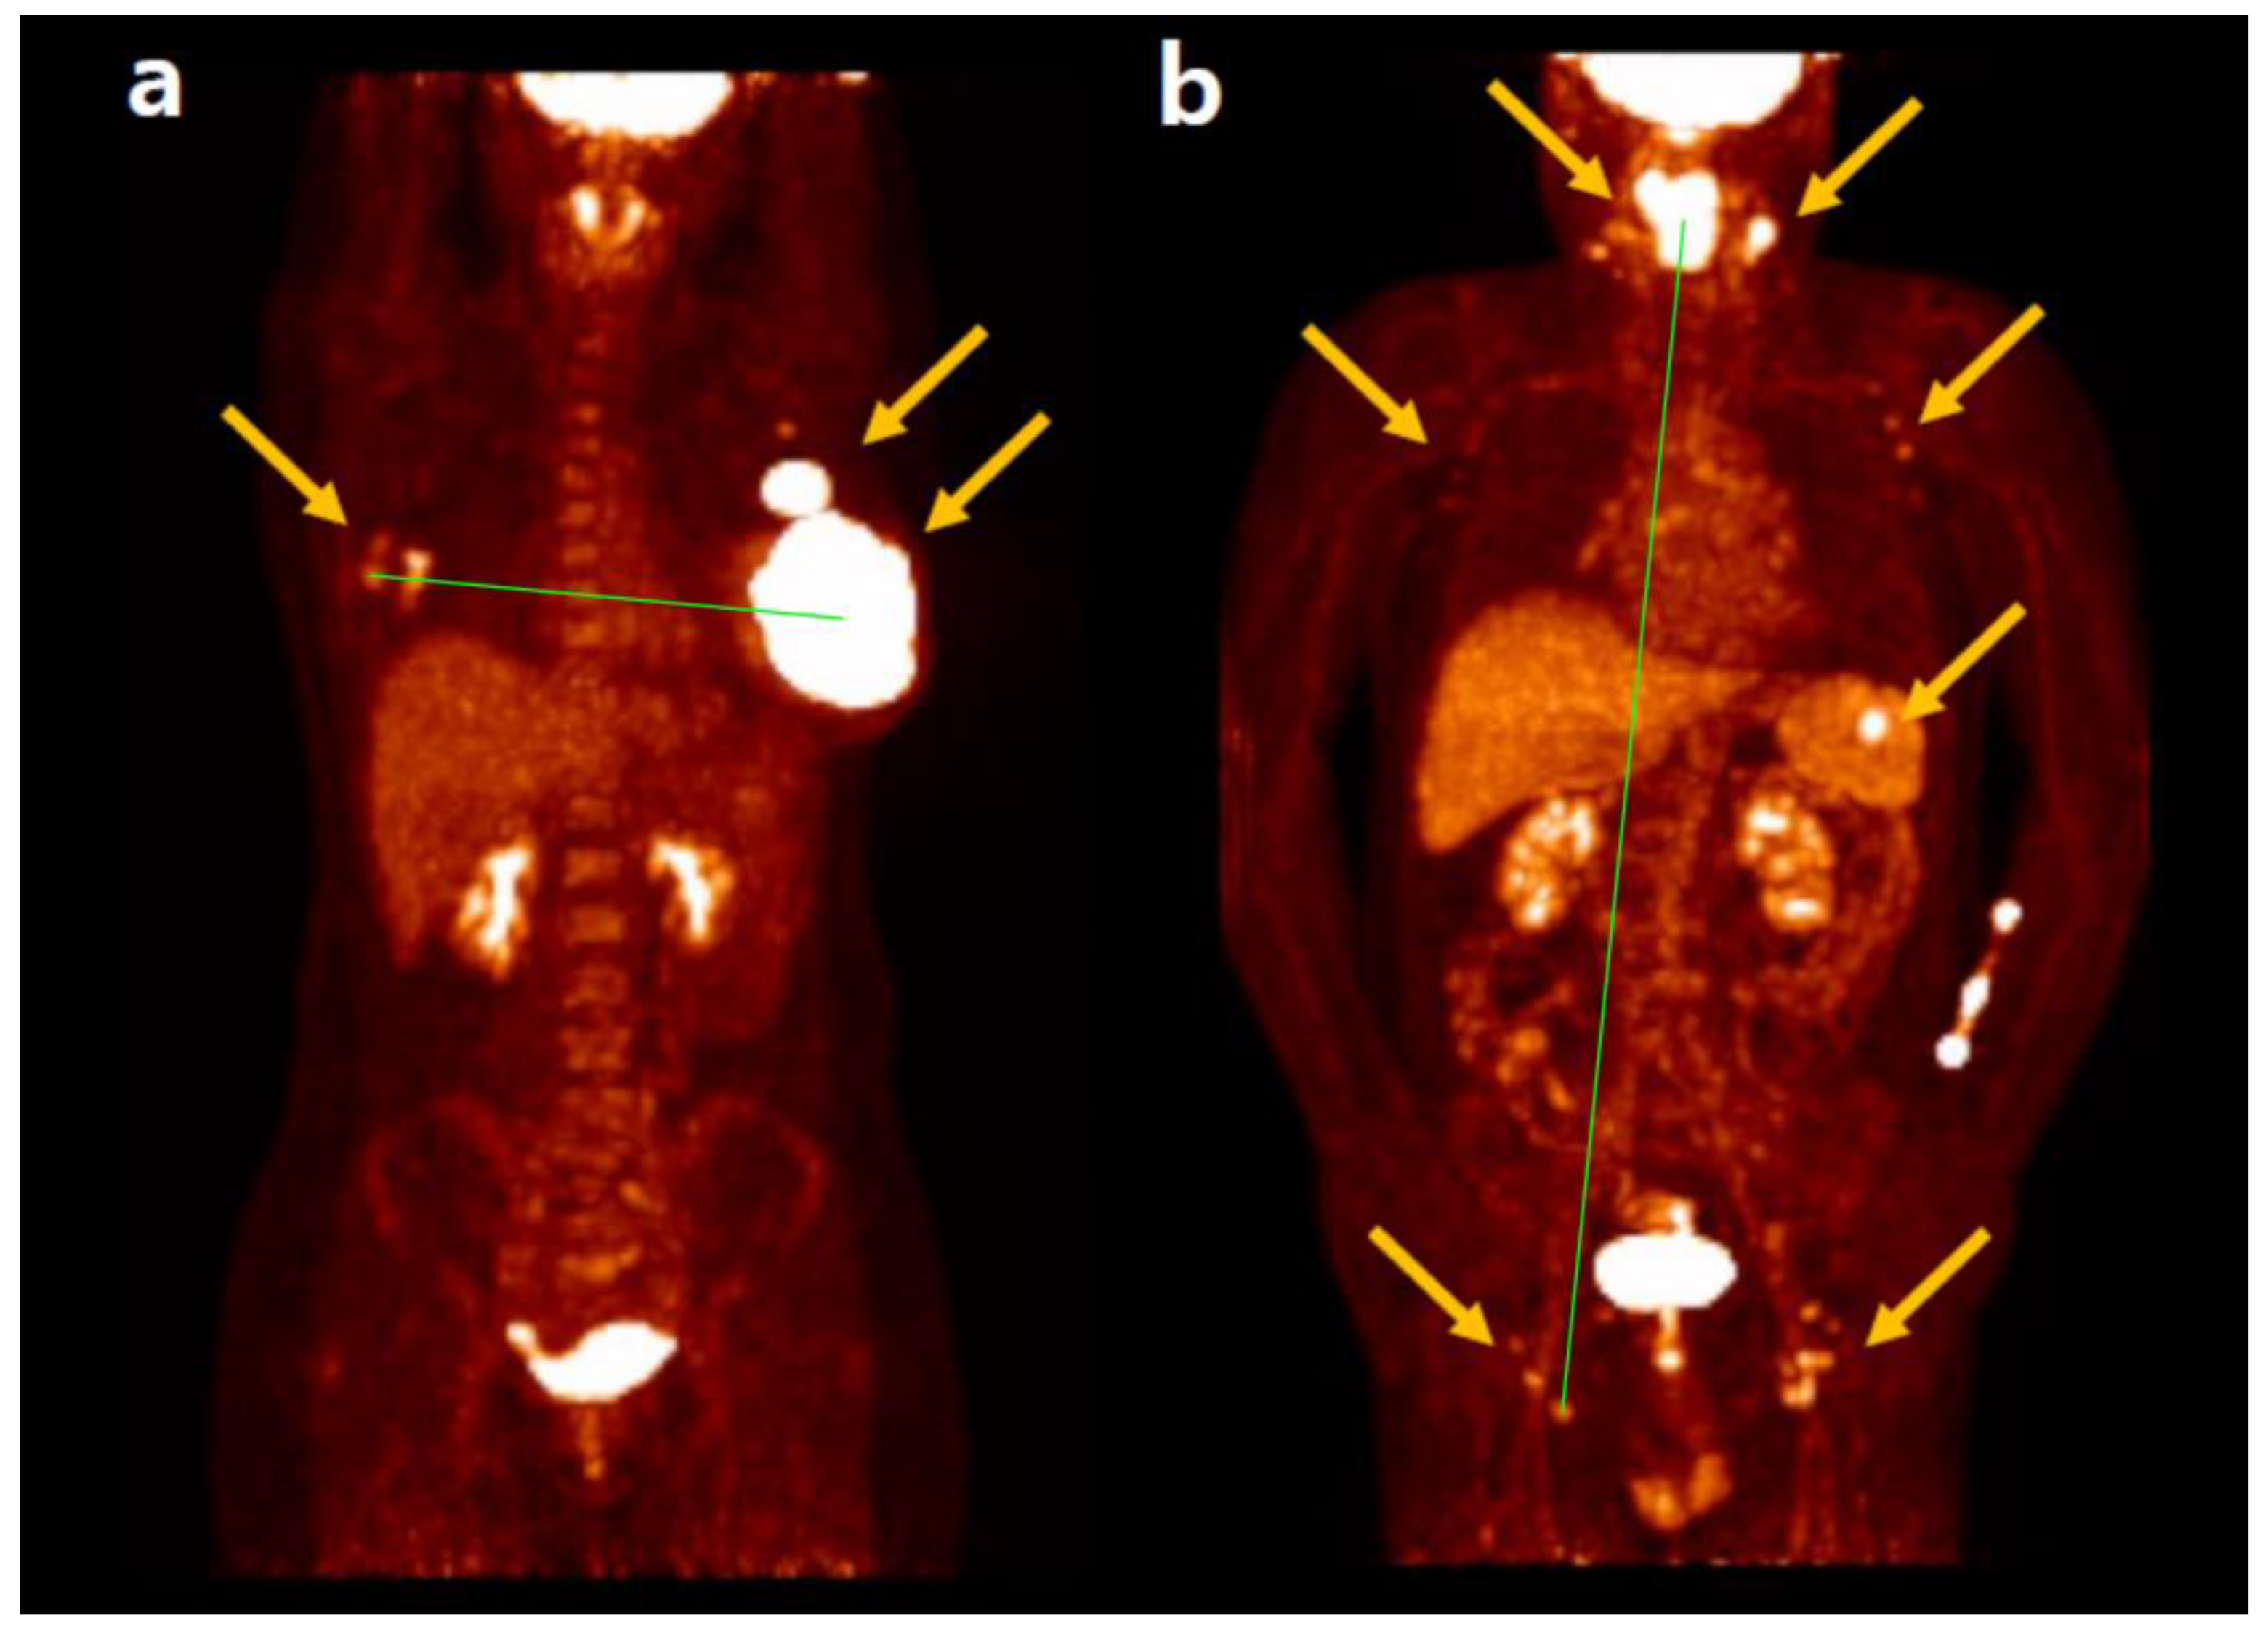

2.3.3. Maximum Tumor Dissemination

The maximum tumor dissemination (Dmax), a concept derived from TMTV, measures the three-dimensional maximum distance between the two FDG-avid lymphoma lesions that are farthest apart. Dmax is a straightforward and intuitive feature to represent tumor burden and dissemination. Because the distance between the center positions of the two tumor lesions is measured automatically after tumor segmentation by software, Dmax is not highly influenced by the operator or tumor contour. Additionally, Dmax can be normalized by body surface area and calculated as standardized Dmax [43]. The significant prognostic role of Dmax in predicting PFS and/or OS has been demonstrated in patients with lymphoma. The most studied lymphoma subtype is DLBCL, followed by HL, with a prevalence of advanced stages (stage III and IV vs. I and II) [44]. Furthermore, Dmax appears to enhance its prognostic value when combined with metabolic variables such as MTV or TLG [45]. Representative cases of Dmax in a patient with DLBCL are shown in Figure 1 [46].